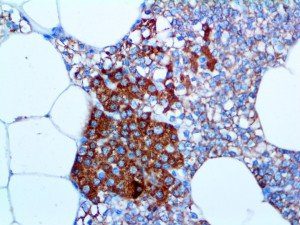

It is the ICU physician who is most likely to witness one of the deadliest manifestations of the abnormal immunological response, the cytokine storm syndrome (CSS). This response is also referred to by some as the cytokine release syndrome (CRS). CSS is characterized by continuous activation and expansion of macrophage and lymphocyte populations, which secrete large amounts of cytokines, causing the cytokine storm. This massive cytokine release is akin to hemophagocytic lymphohistiocytosis (HLH) disease, a syndrome characterized by initial unchecked and persistent activation of cytotoxic T lymphocytes and NK cells.

Clinical and laboratory manifestations of HLH include fever, enlarged liver and/or spleen, neurologic dysfunction, coagulopathy, liver dysfunction, cytopenias (i.e., low levels of erythrocytes, leukocytes, and/or platelets), hypertriglyceridemia, hyperferritinemia, hemophagocytosis, and eventually diminished NK cell activity as the immune system becomes progressively paralyzed. HLH can be familial (primary HLH) or secondary to another disease process (sHLH), such as rheumatic disease, in which it is referred to as macrophage activation syndrome (MAS, characterized by elevated ferritin).